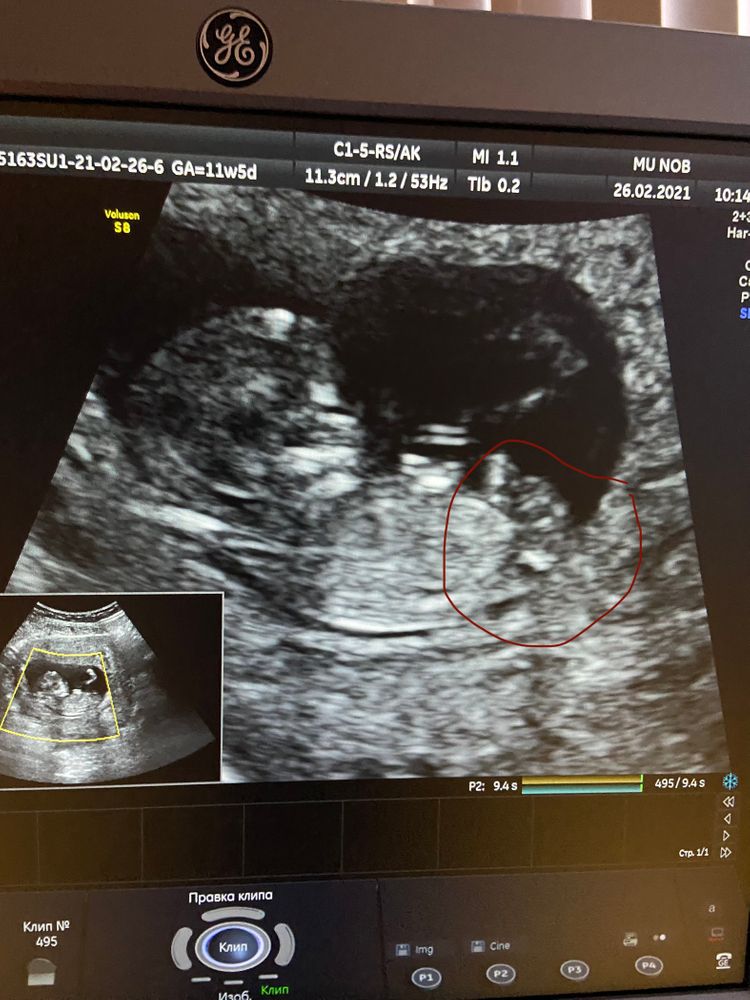

так вот любуюсь я значит своим лялечкой пузяшным, и назрел вопрос , можно ли понять кто ? Мальчик или девочка? Выделила ту часть, что вызвала вопрос😂😂😂

На фото не видно половой бугорок

Похоже на девочку. Бугорок закинут вверх. А если немного вниз опущен-мальчик. Это я на акушерку подписана,она недавно выставляла такие сравнения🙈. Но на какой неделе,не знаю точно.

Ну как по мне то что вы обвели похоже на мужские половые органы, но на этом сроке смотрят половой бугорок сбоку а не так, поэтому тут не определить )

То, что Вы обвели - не то. Это пуповина, скорее всего. Половой бугорок не видно. Ну, мне, по крайней мере))